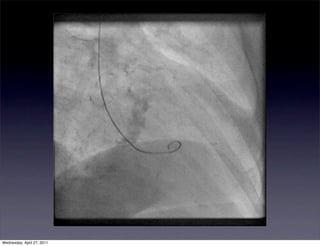

Viability post CABG

•       Methods

•      60 patients undergoing mutlivessel

CABG were studies

preoperatively, 6 days and 6

months post op

•      Patients were also randomized to

be off pump and on pump

•      Exclusion: age > 75 yo, severe pre-

existing LV dysfunction, CKD,

typical MRI contraindications     Selvanayagam et al   DE-MRI in Predicting Viability After CABG                   1539

•       Results

•      Preoporatively 21% of wall                             transmural extent of HE correlated closely with the likelihood     also analyzed by a s

segments had abnormal regional                         of improvement in regional function after surgery (Figure 4).      to good agreement

When all segments that were dysfunctional preoperatively           mural grading of the

function, whereas 14% showed                           were analyzed, the proportion with improved regional func-         the value for asse

evidence of hyperenhancement                           tion decreased as the transmural grade of HE increased             (SE, 0.01; P 0.000

(P 0.001). For example, regional function improved in 156          (Spearman r 0.8; P

•      At 6 months, 57% of wall segments                      of 190 segments (82%) with no preexisting HE but in only 16        by the first and sec

had improved contraction by at                         of 63 segments (25%) with 51% to 75% HE and 1 of 25

Effects of OPCA

segments (4%) with 76% HE. This relationship between the

least one grade                                        transmural extent of HE and the improvement in regional            Global LV Func

•                                                             function was present irrespective of the degree of preopera-       As previously repor

Strong correlation between the                         tive segmental dysfunction (Figure 4).                             was similar in the

transmural extent of                                                                                                      2.9 0.8, OPCABG

CI was significantly

hyperenhancement and ther                              Relationship of New Perioperative HE to Regional

ONCABG; 3.2 0.8

Function at 6 Months

recovery of in regional function at                    To investigate the impact of surgery-related irreversible          Table, the cardiac in

6 months                                               injury on late regional myocardial function and viability, we      · m 2 in the OPCAB

systematically analyzed segments with no or minimal HE             in the ONCABG

Selvanayagam et al Circulation, 2004                  (pre-CABG) in which the RWM worsened at 6 months. In the           improvement in the